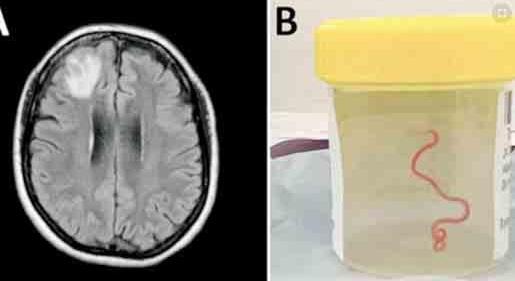

Cuando una mujer australiana de 64 años ingresó en el hospital para someterse a una intervención quirúrgica cerebral, la doctora neurocirujana Hari Priya Bandi no esperaba extraer un gusano parásito vivo de casi 8 centímetros de largo que se retorcía entre sus pinzas. Las pruebas moleculares confirmaron que se trataba de Ophidascaris robertsi, un gusano que suele encontrarse en las pitones.